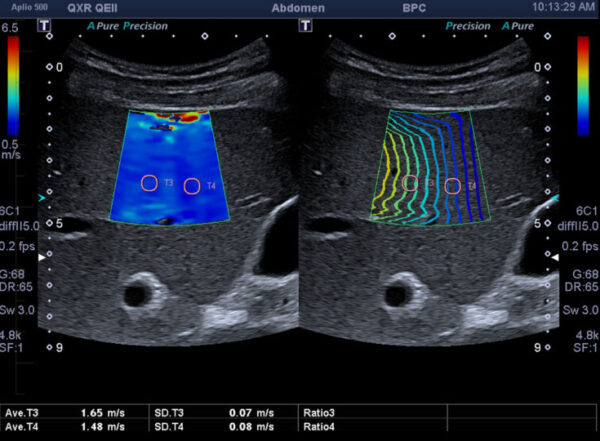

La elastografía surge como una extensión conceptual de la ultrasonografía convencional, pero con un cambio fundamental en el parámetro físico que se desea explorar. Mientras que la ultrasonografía tradicional se…